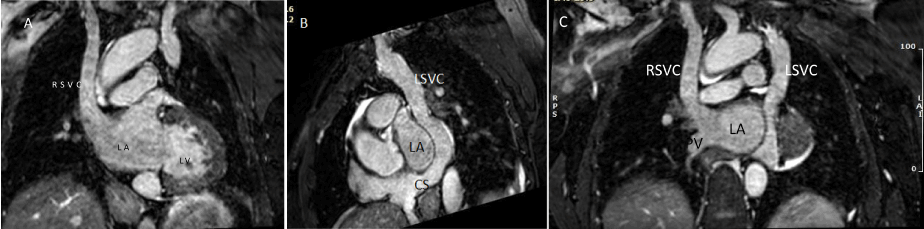

Transthoracic echocardiogram revealed dilated coronary sinus. Agitation saline bubble contrast from right upper extremity showed immediate opacification of the left cardiac chambers suggestive of right superior vena cava draining to left atrium. Transesophageal echocardiogram was performed which confirmed dilated coronary sinus; next, agitated saline bubble contrast injection from the left arm revealed complete opacification of the coronary sinus followed by complete opacification of the right heart, consistent with the presence of the left sided SVC draining to dilated coronary sinus. Cardiac MRI further confirmed findings of a right SVC draining to the left atrium and the left SVC draining to the right atrium (Figure 1A, B and C).

Figure 1A, B &C: Whole heart T2 prep MRI Imaging of 45-year-old adult patient showing bilateral superior vena cavae with right superior vena cava draining to left atrium and left superior vena cava draining to right atrium via dilated coronary sinus.

RSVC: Right superior vena cava; LSVC: Left superior vena cava; LA: Left atrium; LV: Left ventricle; RA: Right atrium; CS: Dilated coronary sinus; PV: Pulmonary vein